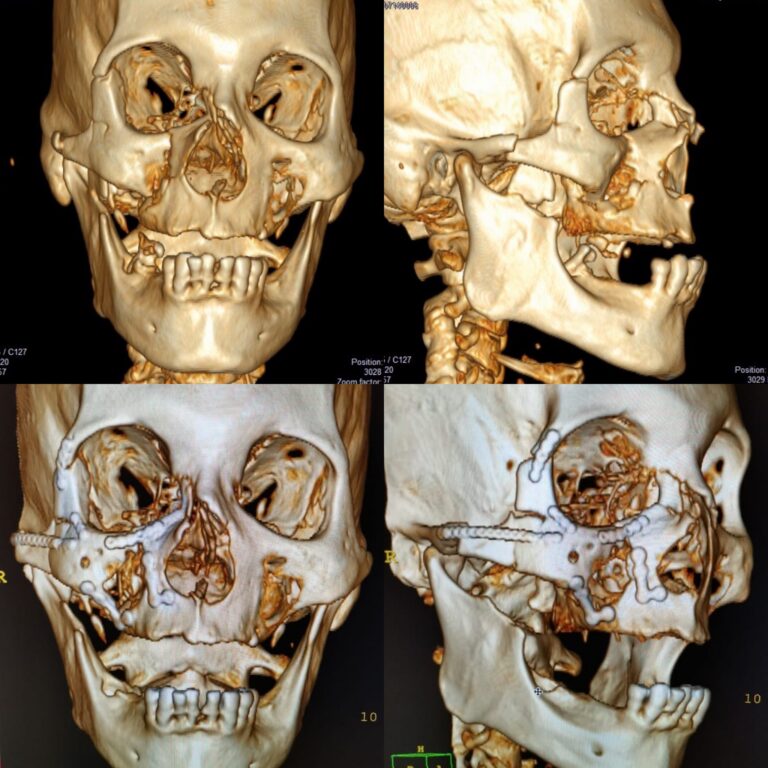

Reconstrucción de Trauma Facial

La reconstrucción de un trauma facial es un procedimiento quirúrgico que se realiza para...

Cirugía Ortognática en Asimetría de mandíbula por Hiperplasia de cóndilo

La cirugía ortognática puede ser una solución para corregir la asimetría de la mandíbula causada por...